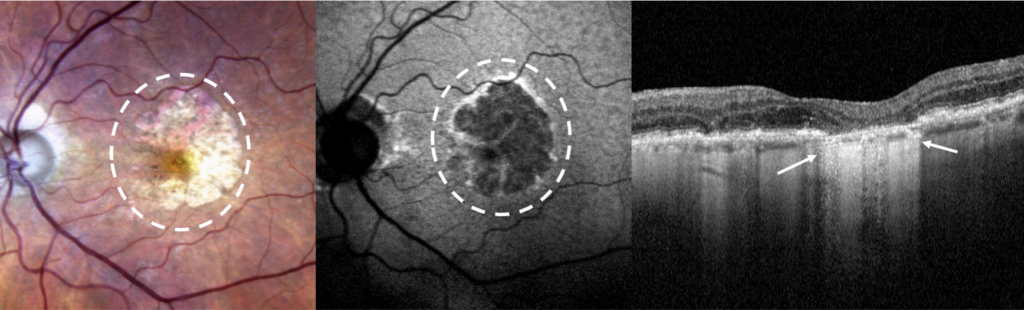

Lors du bilan, l’acuité visuelle est mesurée par l’orthoptiste. Ensuite un OCT maculaire permet de mesurer l’épaisseur de la macula et scanner la rétine à la recherche de signe d’atrophie. Une photo de l’aire maculaire est prise en couleurs et en auto fluorescence. Ce filtre met en évidence le nombre et l’étendu des plages d’atrophies. En cas de doute, sur une forme « humide » ces examens seront complétés par le module OCT Angiographique  (OCT-A) pour éliminer la présence de néovaisseaux. Ces mesures servent au diagnostique mais aussi à la surveillance de la DMLA.

Rétinophoto couleurs et autofluorescente avec plage d’atrophie géographique maculaire (pointillés). Coupe OCT avec atrophie rétinienne et de l’épithélium pigmentaire (flèches).